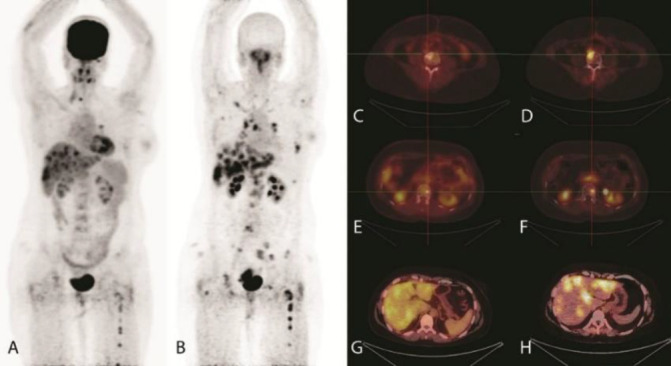

Results: Physiologic distribution of [68Ga]-Ga-FAPI-46 was observed in the liver, blood pool and kidneys, whereas no tracer uptake was noted in the brain and heart. The mean liver SUVmax for [68Ga] Ga-FAPI-46 was 1.5±0.1 which was lower than that noted for [18F]-FDG PET/CT (2.9±0.2). Likewise, the mean blood pool SUVmax value for [68Ga]-Ga-FAPI-46 was lower than [18F]-FDG PET/CT (1.7±0.1 versus 2.0±0.1). [68Ga]-Ga-FAPI-46 PET/CT demonstrated higher tracer uptake in the lesions detected in the brain, bone, internal mammary and lymph nodes in 4/12 patients. The overall lesions detections and the mean SUVmax values did not differ significantly between the two techniques. On the other hand, [68Ga]-Ga-FAPI-46 demonstrated higher mean TBRmax than [18F] FDG PET/CT particularly for lesions detected in kidneys, chest wall, mediastinum, and musculoskeletal lesions. However, both techniques offered identical TNM staging.

Conclusion: The findings of this preliminary study demonstrated that [68Ga]-Ga-FAPI-46 and [18F]-FDG PET/CT offered identical disease staging in the breast cancer patients. [68Ga]-Ga-FAPI-46 showed lower liver and blood pool uptake and an enhanced tumor-to-background ratio, thereby suggesting its potential for improved lesions detection. This may open opportunity for emerging FAP based radioligand for therapeutic applications in advanced stage breast cancers. However, this needs validation in a larger number of patients.